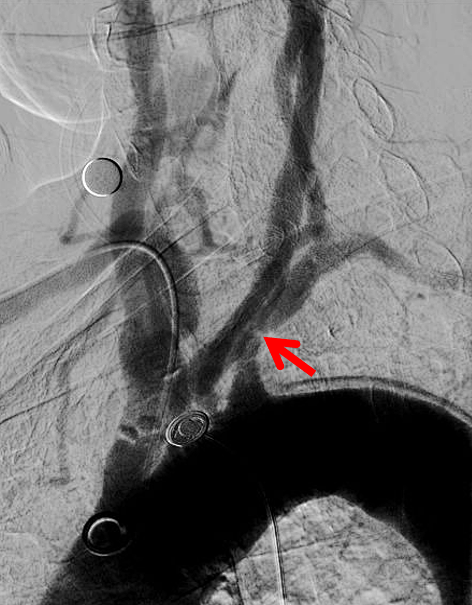

III型弓;左侧锁骨下动脉重度狭窄

经左桡动脉逆向造影显示左侧锁骨下动脉重度狭窄